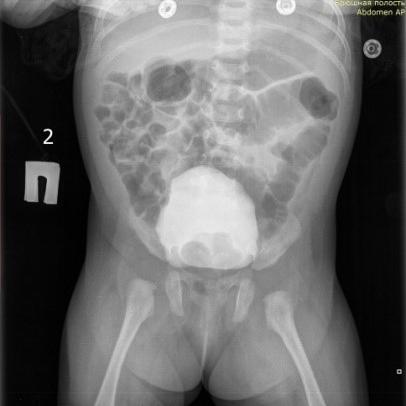

Особенности CAKUT-синдрома: клинический случай.